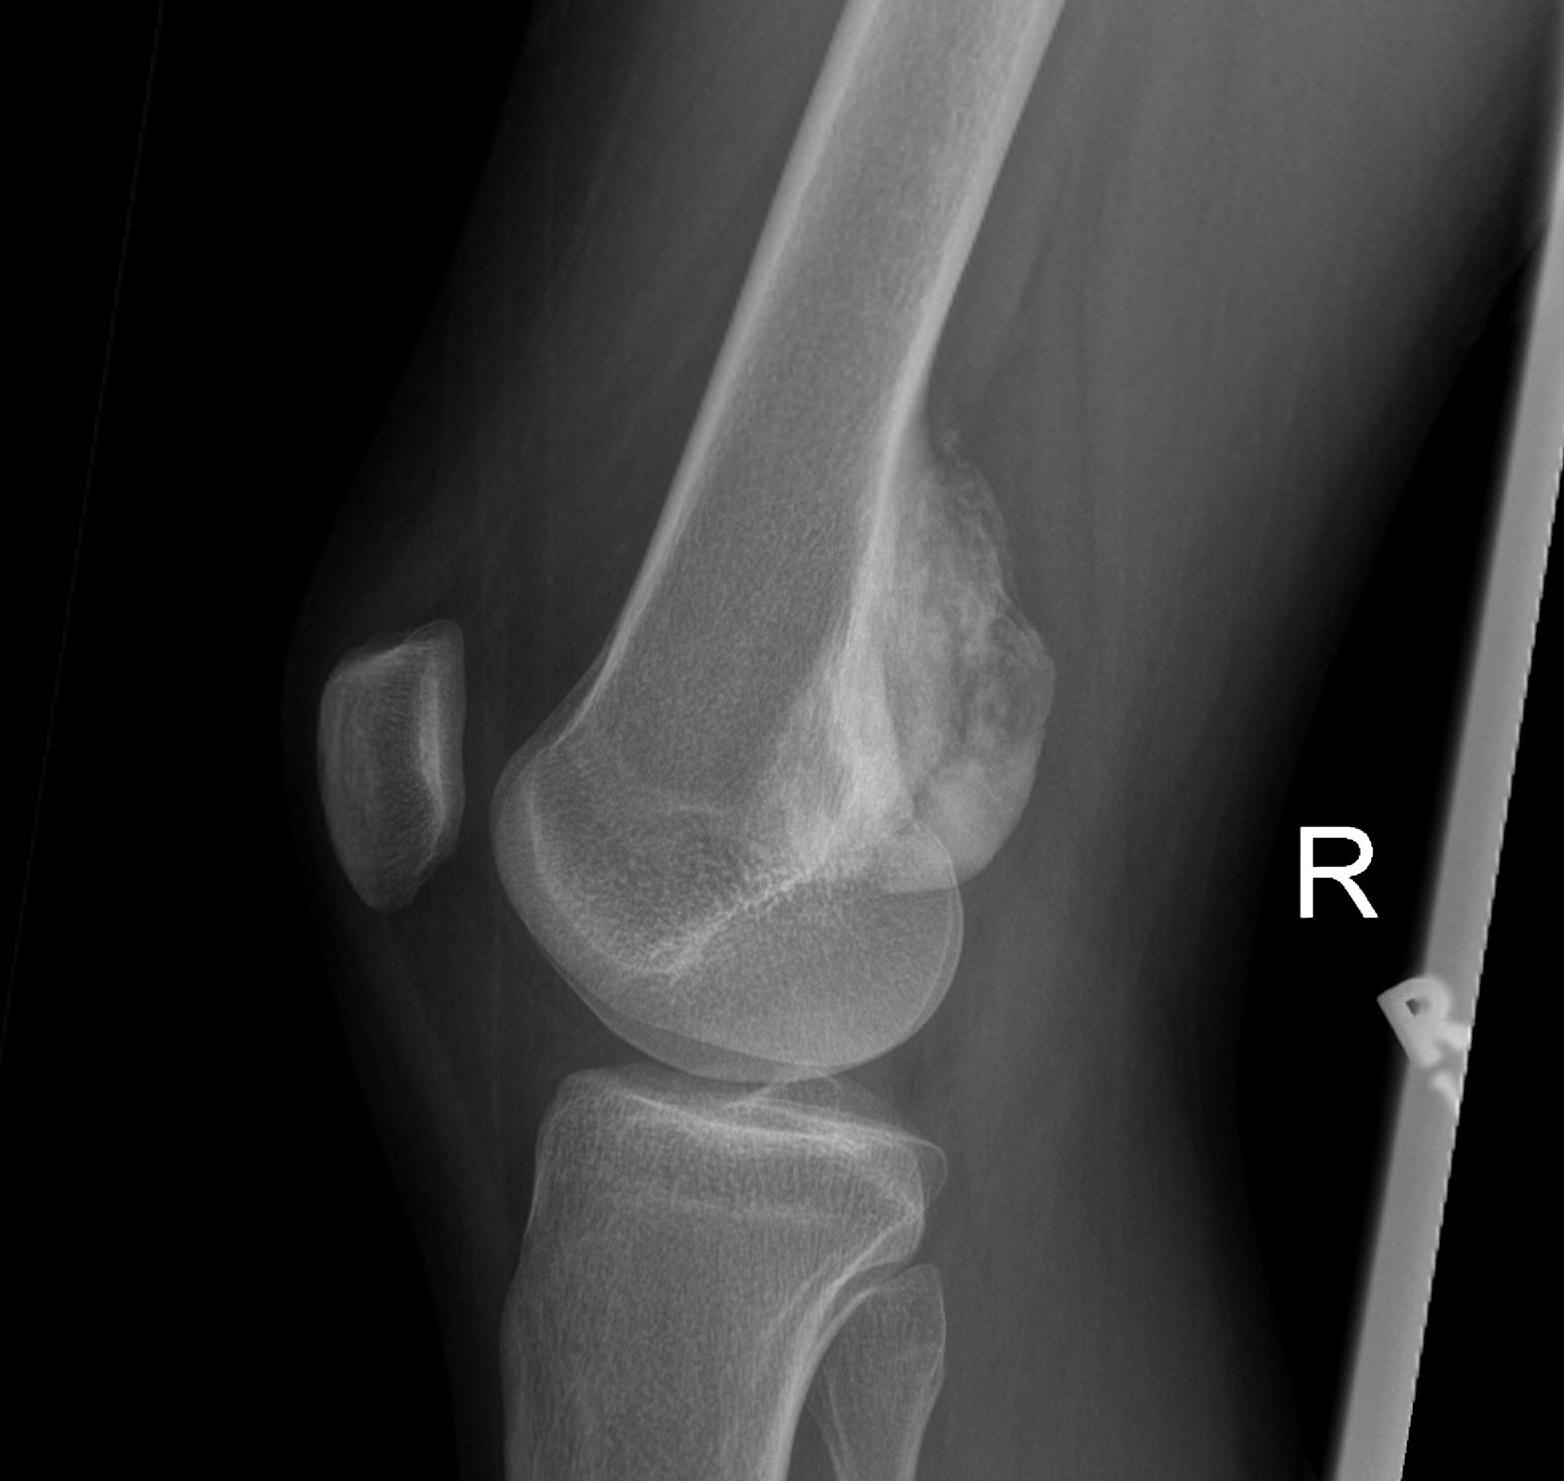

Popliteal fossa / parosteal OS

- posterior approach

- go through hamstrings or gastrocnemius

- depending on whether lesion medial or lateral